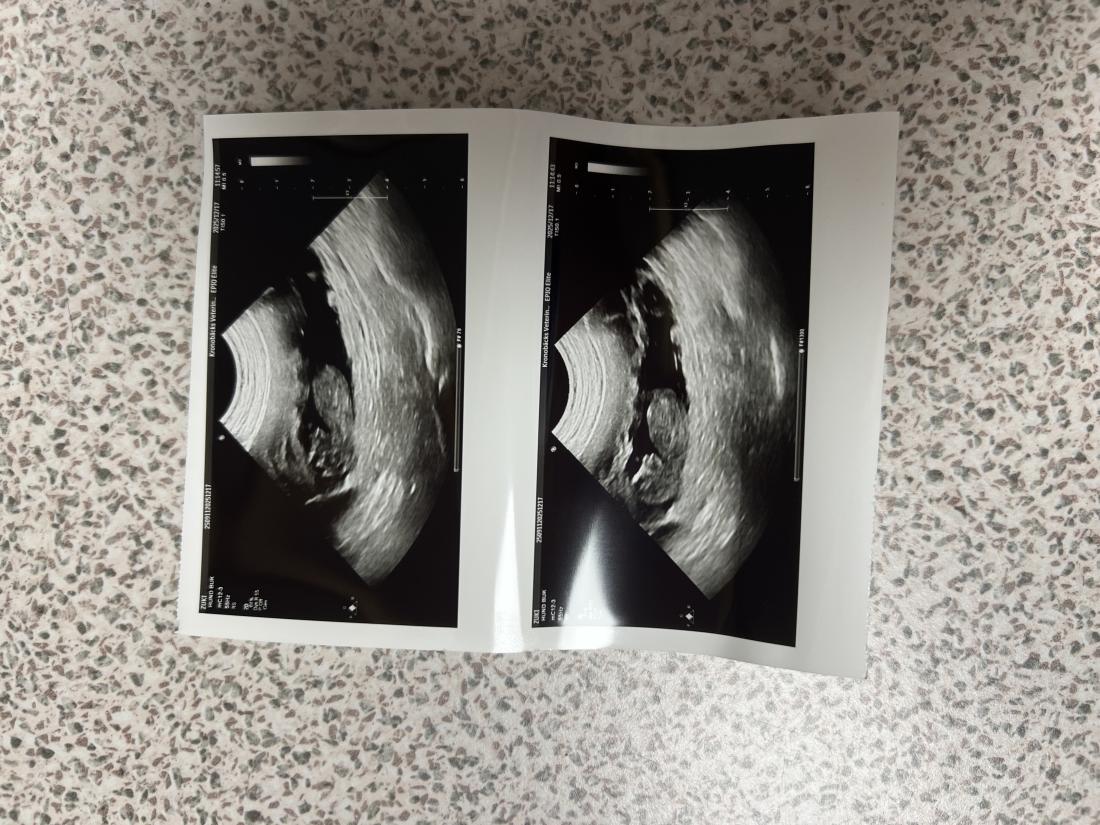

Under gårdagen när vi verkligen konstaterat att varken Doris eller Alfons var intresserade av någon dejt, helt enkelt på grund av att löpet var över - behövde vi tänka om. Vi har ju planerat för detta och har även flera valpköpare som går med längtande hjärtan efter en av våra valpar. ❤️ I samma veva inser vi att Milla också bör vara i höglöp. Vi behövde dividera OM det skulle vara en bra idé. Stämde av med Millas matte såklart. Men efter noggrant övervägande ville vi ge det ett försök. Millas matte hann knappt ut genom dörren innan Milla och Alfons funnit varandra igen 🫣😂 👩‍❤️‍💋‍👨.

Vi fick alltså smida om våra planer i all hast, men nu räknar vi ner efter valpar igen. Inte till vilka valpar som helst - till den helt otroliga kombinationen Milla & Alfons. Ni som följde oss under 2024 vet ju vilken helt fantastisk kombo det blev 😮‍💨. Det finns fortfarande några platser kvar att boka för er som inte vill missa denna chans. Förväntad valpning blir till påsk och leverans runt 11 juni. 🌸